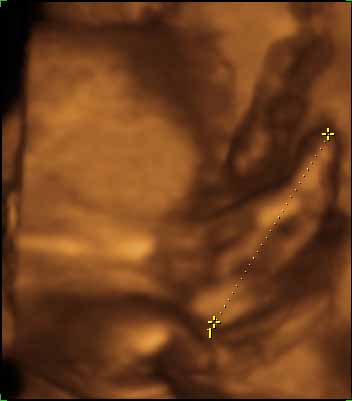

Tegnapi uhu: minden rendben - ez már nem megy olyan csoda számba... na jó, azért persze az. A doki kedves volt, úgy látszikmegérte az eddig belefektetett pénzt. Kikérdezte h mikor kell bemenni a koriba... Marcell baba feje 67mm, lábszára pedig 48. kérdeztem h mekkora lehet a súlya, azt mondta hogy azt sose akarjam tudni...